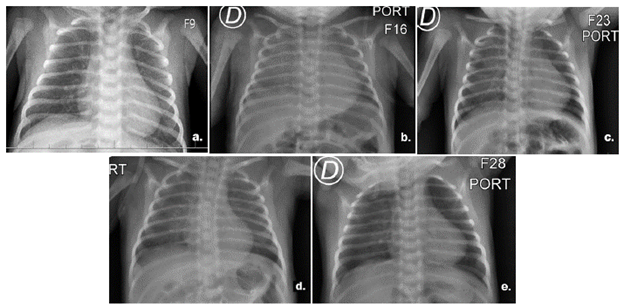

Pasadas las 6 horas postransfusión, el paciente se encontró en regulares condiciones generales, con aspecto séptico e incremento del esfuerzo respiratorio, por lo que se consideró inicialmente una sepsis neonatal tardía de origen viral. Se le realizaron exámenes de control de perfil infeccioso con resultado de procalcitonina negativa, el análisis citoquímico de líquido cefalorraquídeo estuvo dentro de parámetros de normalidad y una serie de radiografías de tórax que inicialmente evidenciaron velamiento en ambos hemitórax con predominio derecho y posteriormente presentó una leve mejoría del patrón radiológico (Figura 1).

Mediante la auscultación cardiopulmonar se identificó un soplo protosistólico grado III/VI, y con base en el antecedente transfusional y la clínica instaurada se determinó como diagnóstico TRALI, se descartó sepsis de origen pulmonar y los resultados de panel viral respiratorio y hemocultivos seriados fueron negativos. Pasadas las 24 horas de instaurado, el cuadro clínico resolvió de forma espontánea y finalmente el paciente resolvió el cuadro clínico y se le dio egreso.

En este caso, los exámenes no demostraban un origen infeccioso de la patología en curso; el reporte de los reactantes de fase aguda, tanto los hemocultivos como el análisis citoquímico de líquido cefalorraquídeo fueron negativos. Sumado a esto, al tener en cuenta el patrón radiológico observado y la evolución súbita del cuadro clínico del paciente a nivel respiratorio, caracterizada por disnea, retracciones subcostales, así como la reacción eritematoso-vesiculosa presentada en el tronco, se consideró cuadro de TRALI secundario a la transfusión.